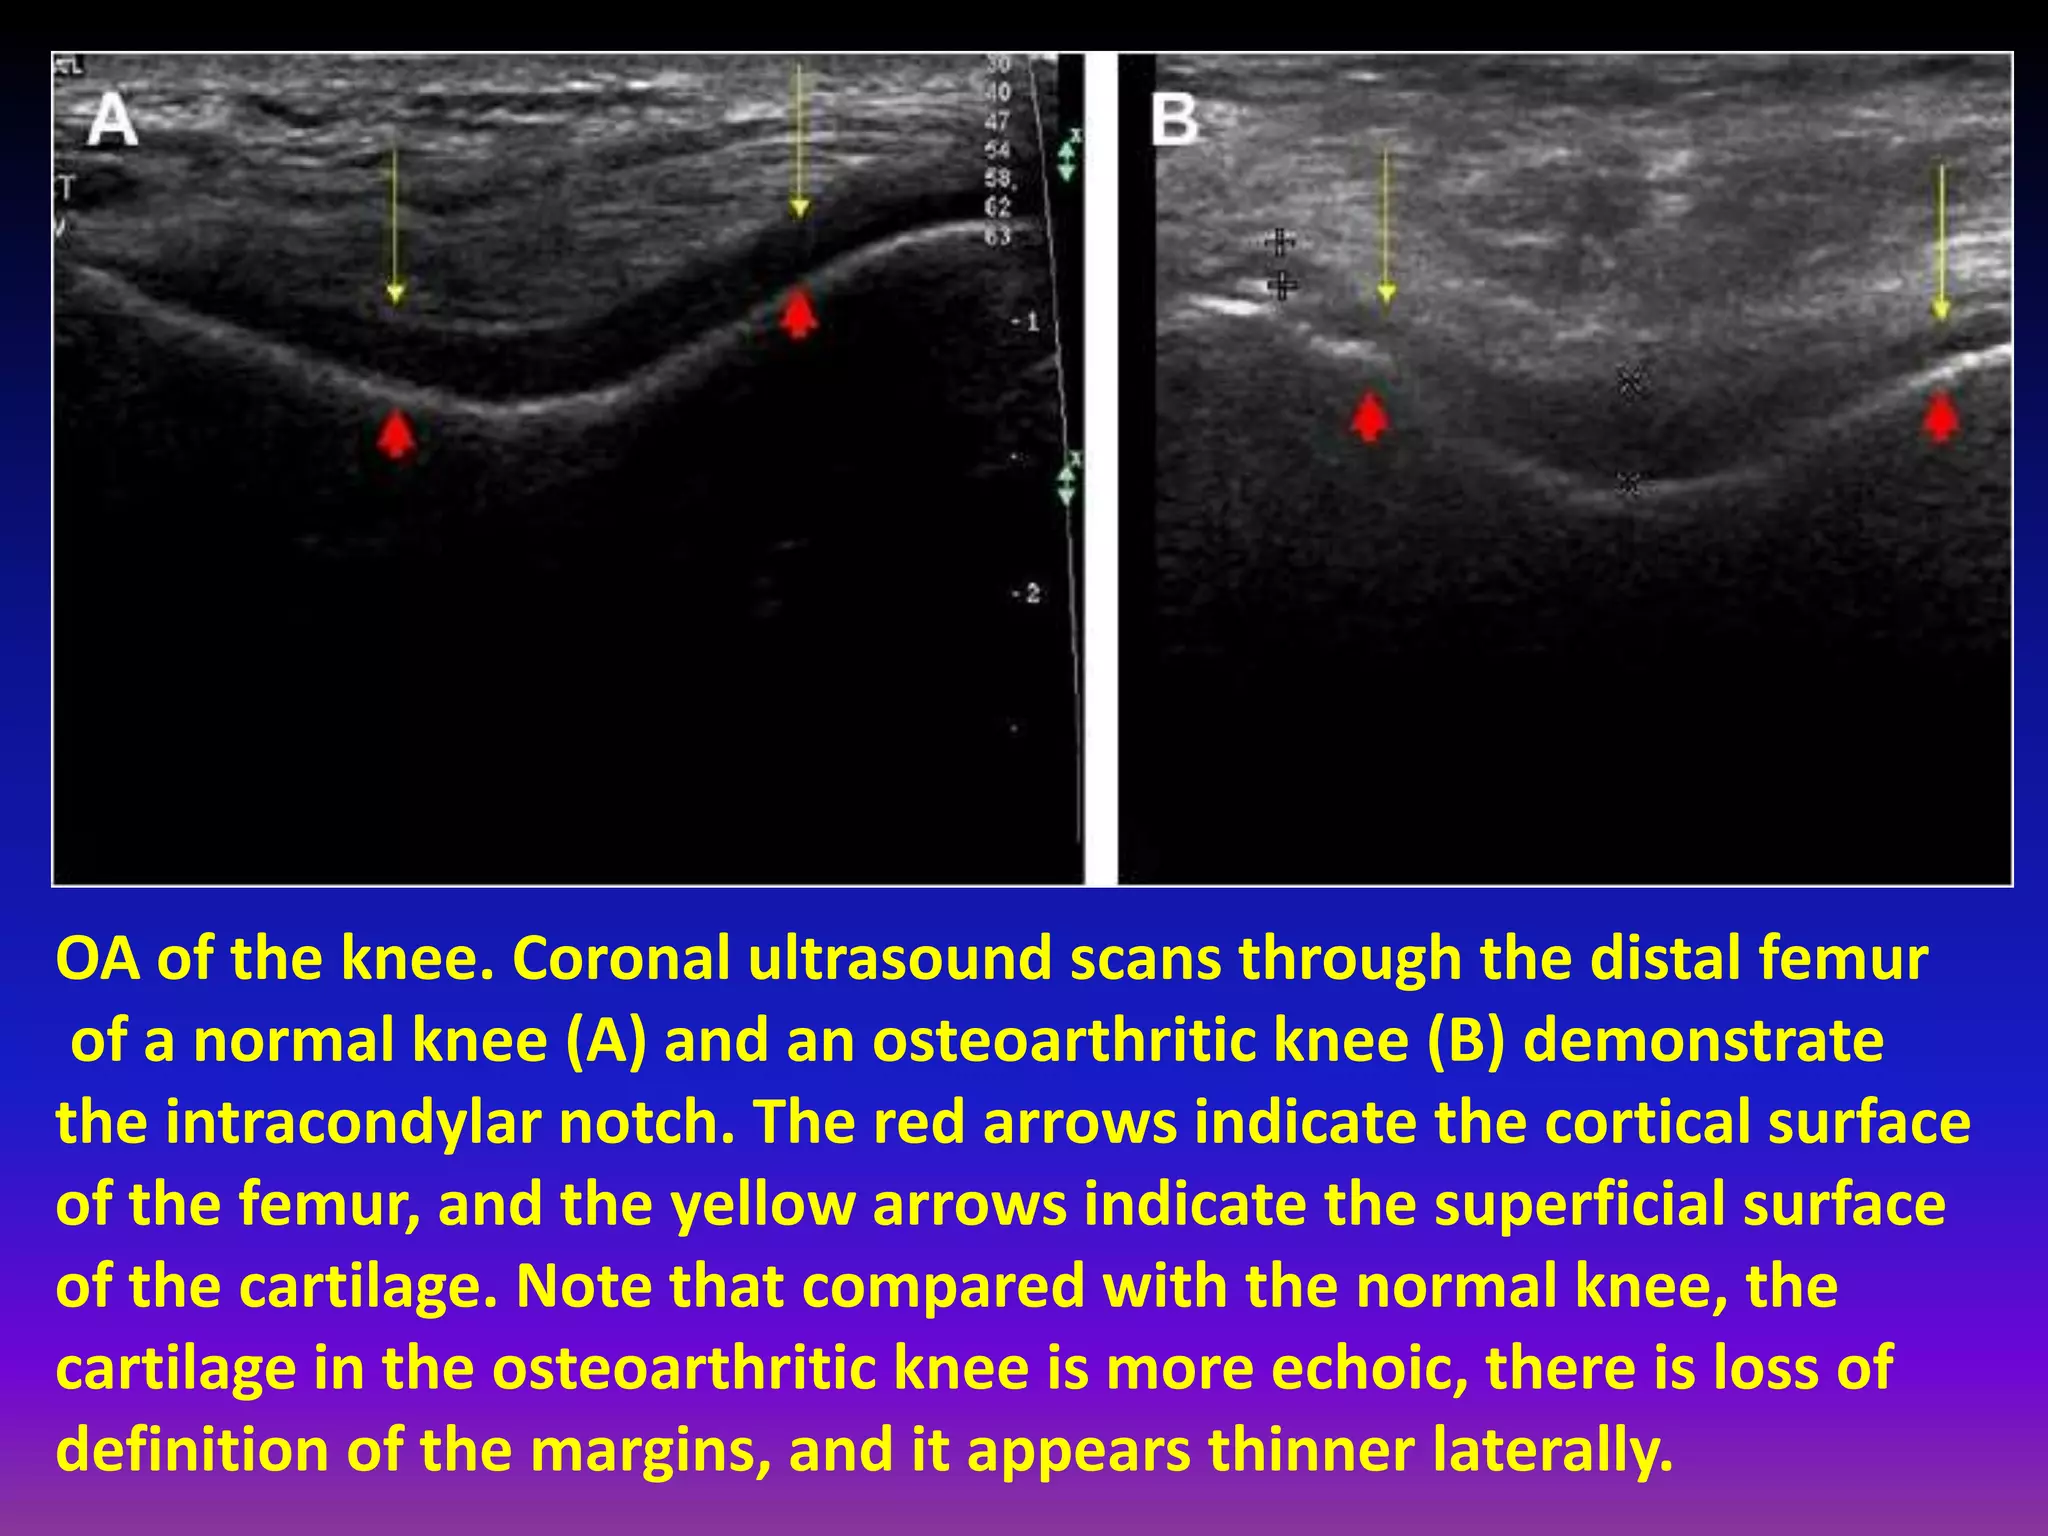

OA of the knee. Coronal ultrasound scans through the distal femur

of a normal knee (A) and an osteoarthritic knee (B) demonstrate

the intracondylar notch. The red arrows indicate the cortical surface

of the femur, and the yellow arrows indicate the superficial surface

of the cartilage. Note that compared with the normal knee, the

cartilage in the osteoarthritic knee is more echoic, there is loss of

definition of the margins, and it appears thinner laterally.

Ultrasound.

Visualization in multiple planes.

Real time, dynamic assessment.

No radiation and in expensive.

But, no visualization of deep articular cartilage.

Low contrast between cartilage and fluid.

Low negative predictive value.